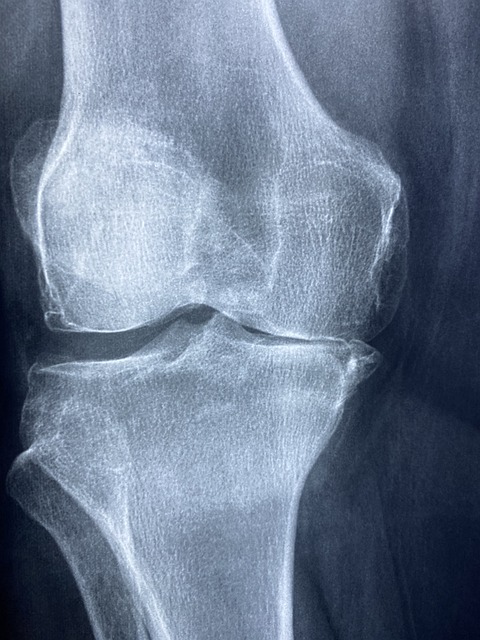

무릎 통증원인 - 퇴행성 관절염 퇴행성 관절염은 나이가 들면서 발생하는 관절의 퇴행성 변화로 인해 무릎 통증을 유발합니다. 연골이 닳아 없어지면서 뼈와 뼈가 서로 마찰되어 통증과 염증을 일으킵니다.

- 반월상 연골 파열 반월상 연골은 무릎 관절 내에서 충격을 흡수하는 역할을 합니다. 스포츠 활동이나 갑작스러운 움직임으로 인해 이 연골이 찢어질 경우, 심한 통증과 부기를 초래할 수 있습니다.

- 십자인대 손상 십자인대는 무릎의 안정성을 유지하는 데 중요한 역할을 합니다. 축구, 농구 등 격렬한 운동 중에 십자인대가 손상되면 무릎 통증과 함께 불안정성이 발생합니다.